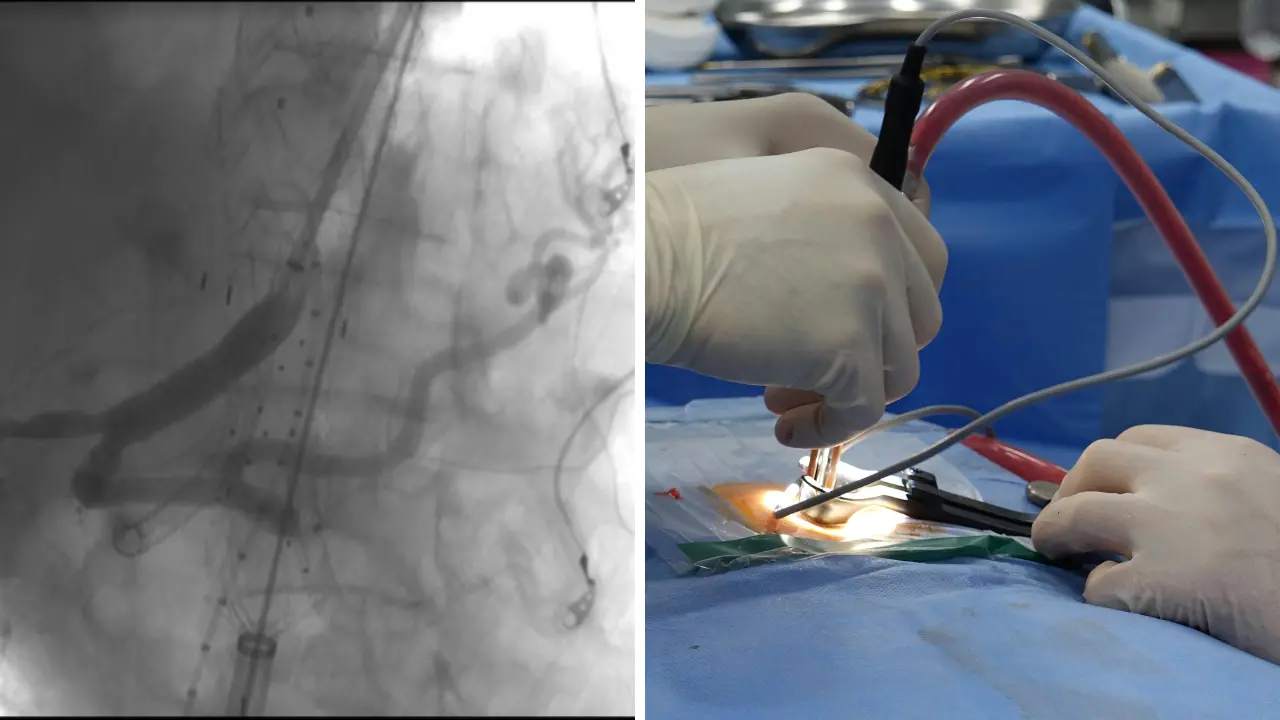

È stato eseguito con successo, all’Uoc Chirurgia Vascolare del Grande Ospedale Metropolitano di Reggio Calabria, un trattamento di elevata complessità su un paziente con un voluminoso aneurisma toraco-addominale (7 cm di diametro).

L’aneurisma toracico è stato trattato con un approccio endovascolare, mediante il posizionamento di endoprotesi; successivamente è stata posizionata un’endoprotesi ramificata per i vasi viscerali ed una terza endoprotesi aorto-bisiliaca. Il decorso post-operatorio è stato ottimale: il paziente non ha avuto complicanze ed è stato dimesso al proprio domicilio in buone condizioni di salute.

Le tecniche endovascolari avanzate consentono di trattare tali patologie complesse che altrimenti prevedrebbero un trattamento chirurgico tradizionale gravato da un elevato tasso di mortalità e da lunghi tempi di degenza in terapia intensiva.